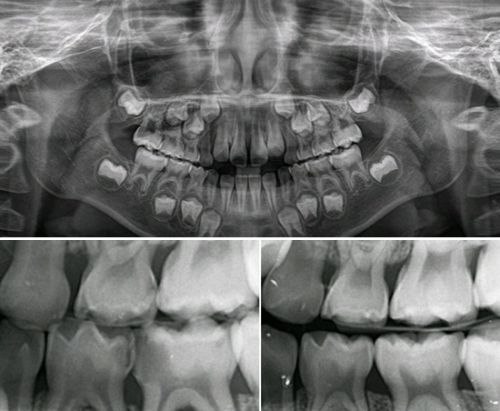

그리고 이어서 빠질 수 없는 검사가 바로 방사선 검사입니다. 구강 내에서 촬영하는 작은 엑스레이 사진부터, 턱 전체를 찍는 파노라마 사진, 치과용 컴퓨터단층방사선사진(CT)까지 종류가 다양합니다. 육안으로는 볼 수 없는 치아 속 구조나 잇몸뼈 상태, 혹은 염증이나 낭종 같은 병적인 상태를 파악하는 데 꼭 필요한 검사입니다.

하지만 많은 분들, 특히 아이를 데려오신 보호자분들께서 “방사선은 몸에 해로운 것 아닌가요?”하고 걱정하시고 질문하시면서 촬영하기를 꺼리시는 분들이 꽤 많이 있습니다. 그래서 그분들을 안심시켜드리는 것이 치과 의료진의 중요한 업무중의 하나입니다.

치과에서 사용하는 방사선은 매우 적은 양이며, 실제로 입안 엑스레이 한 장을 찍을 때 나오는 방사선량은 우리가 평소 일상생활에서 자연스럽게 햇볕을 통해 받는 양과 비슷합니다. 게다가 촬영 시에는 납으로 된 방호복을 입고 검사하기 때문에 그나마도 대부분 차단이 됩니다.